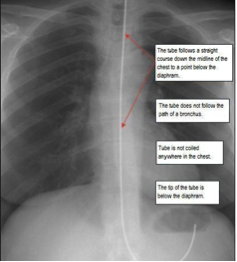

Nasogastric feeding tube

• Passed through the nose, down the oesophagus and into the stomach

• Generally used for short term feeding